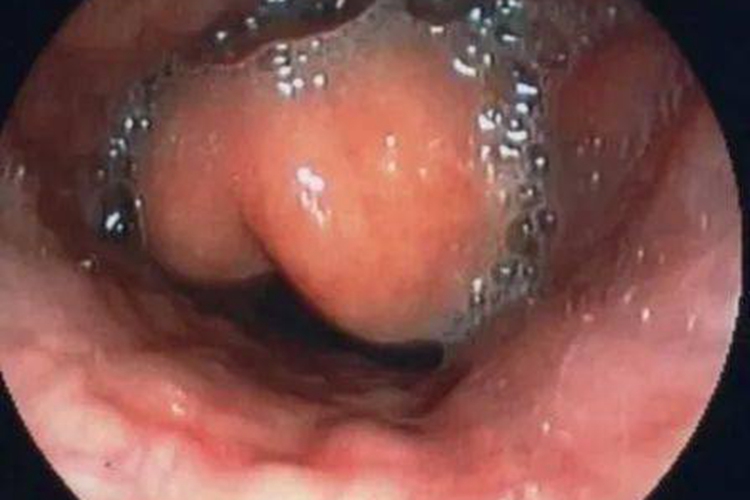

会厌炎即急性会厌炎,起病急,患者会出现会厌肿胀,伴有畏寒发热、剧烈咽喉痛等症状,吞咽时疼痛加重,症状严重时连唾液也难咽下。会厌高度肿胀时可引起吸气性呼吸困难,甚至窒息。间接喉镜检查可见会厌明显充血、肿胀,严重时呈球形。